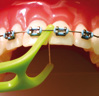

È POSSIBILE PASSARE IL FILO INTERDENTALE CON L’APPARECCHIO FISSO

É possibile passare il normale filo interdentale, aiutandosi con aghi passafi lo che ne facilitano l’inserimento tra i denti e apparecchio, oppure con fili interdentali appositi per apparecchi ortodontici, dotati di un’estremità più rigida che ne agevola lo scorrimento. Passare il fi lo interdentale tra dente e dente, facendolo scorrere sotto arco ortodontico, pulire la zona gengivale, strofinare il filo interdentale lungo la superficie dei denti e delicatamente attorno agli attacchi, cambiando il filo quando sporco.